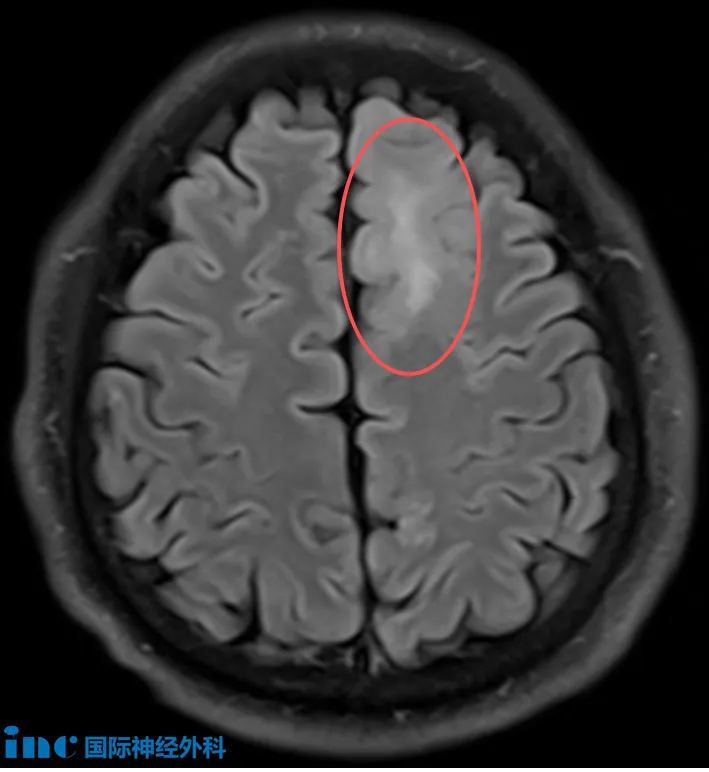

48岁的孙先生,在当地医院体检头颅核磁,发现左侧额叶存在异常信号。为进一步明确诊断,他进行了PET-MRI检查,结果提示:左额叶近中线异常信号,考虑低级别胶质瘤可能性大(脱髓鞘病变不除外)。随后的头颅MRI确认了左额叶皮层及皮层下存在边界不清的异常信号,范围约41×28mm,增强扫描未见明显强化。令家属担忧的是,孙先生近来已出现记忆力下降的迹象。面对这个超过4厘米、性质未明的脑内病灶,到底是什么,要不要手术?

“归根结底,我们从来无法从影像获得百分之百的确定性。手术是获得准确诊断的唯一方法。即便影像显示这是肿瘤,我们仍然不了解肿瘤的分子特征,而这也是非常重要的。我会尽可能多地切除,但同时我们也不希望损伤或影响功能。”——INC巴教授